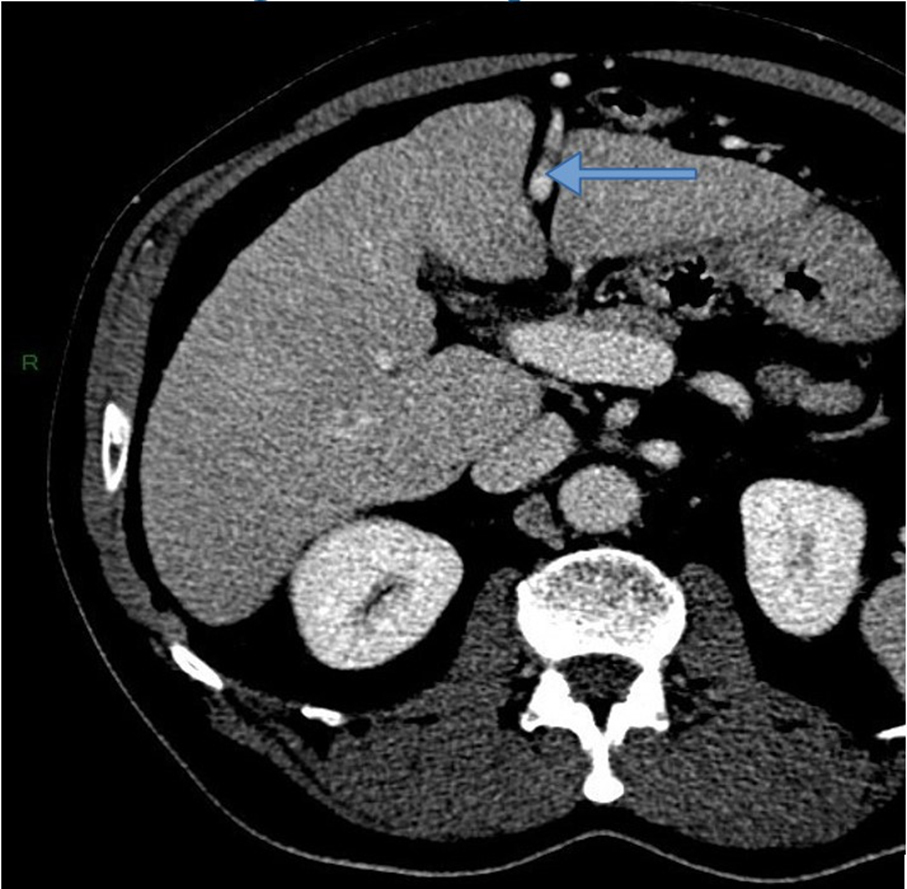

À l’examen clinique, vous retrouvez des signes d’insuffisance hépatocellulaire et d’hypertension portale associés à une hépatomégalie homogène à deux travers de doigts avec un bord inférieur tranchant. Le patient est marbré. Il existe une discrète ascite sans encéphalopathie associée. La palpation abdominale est indolore. Les constantes sont les suivantes : tension artérielle (TA) à 95/55 mmHg, pouls à 130/min, saturation en oxygène (SaO2) à 98 %, apyrétique.